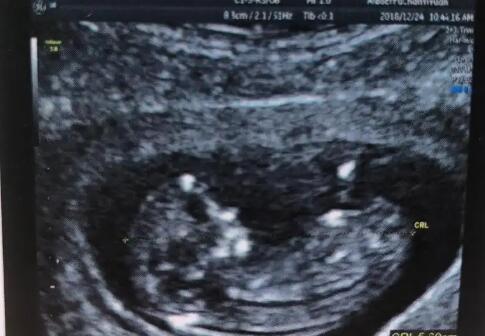

南宁市做试管婴儿的价格 2022年南宁可以包生男生试管医院分享 ‘彩超下的男孩’